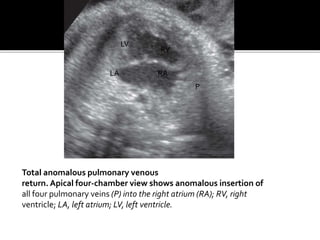

Total anomalous pulmonary venous

return. Apical four-chamber view shows anomalous insertion of

all four pulmonary veins (P) into the right atrium (RA); RV, right

ventricle; LA, left atrium; LV, left ventricle.

Total anomalous pulmonaryvenous return. Apical four-chamber view shows anomalous insertion of all four pulmonary veins (P) into the right atrium (RA); RV, right ventricle; LA, left atrium; LV, left ventricle. LV LA RA RV P